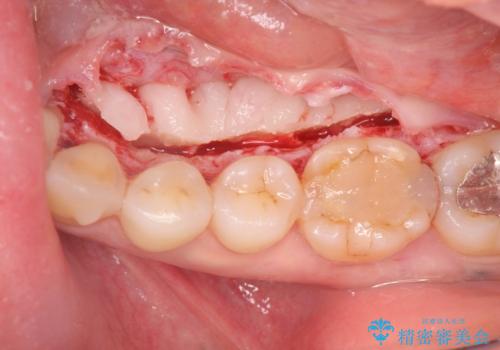

話すのに邪魔な、下顎骨隆起の切除

- 矯正治療を開始するのに伴い、滑舌を含めた改善を計るために、発音の邪魔となる下顎骨隆起の切除を計画します。

手術時間は約30分程度(大きさにより)今回は手術中に、静脈麻酔を行うことで負担なく治療を行う計画としました。

長年気になっていた骨隆起が短時間でなくなり、満足いただくことができました。